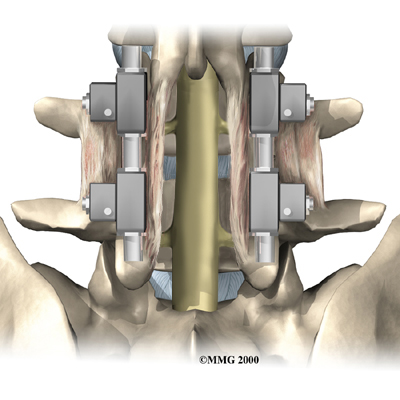

During posterior spinal fusion, the surgeon also fixes the bones in place using a combination of metal screws, rods, and plates. This instrumentation (or hardware, as it is sometimes called) holds the vertebrae to be fused together and prevents them from moving. The less motion there is between two bones trying to heal, the higher the chance they will successfully fuse. The use of instrumentation has increased the success rate of spinal fusions considerably.

When instrumentation is used, the screws, rods, or plates can also cause problems. They can loosen and irritate the nearby soft tissues. In rare cases, they may actually break. If your hardware loosens or breaks, the surgeon may suggest another surgery either to take out the hardware or to add more hardware to solve the problem.

In the second procedure, the surgeon usually adds more bone graft. Metal plates and screws may also be added to rigidly secure the bones so they will fuse together.